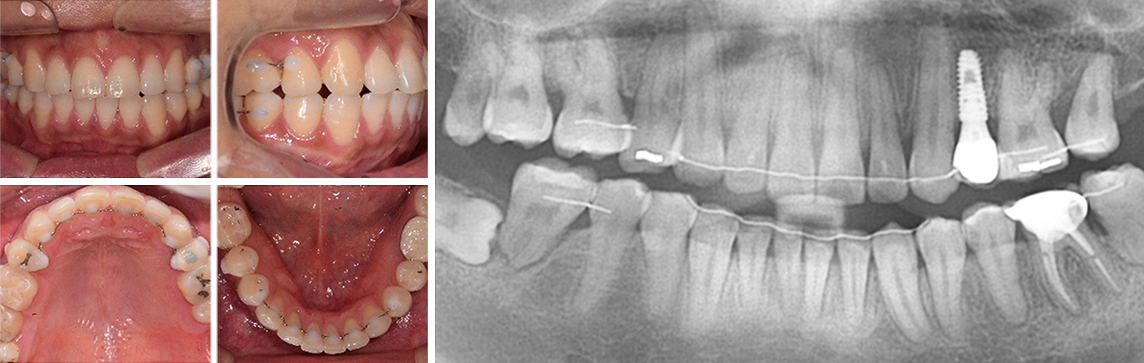

30대 남환으로 다른 치과에서 임플란트 5개 진단을 받고 내원. 교정과 협진으로 공간을 메꾸고 오른쪽 위 치아에 임플란트를

1개만 식립하여 자연치아를 최대한 활용하는 진료 계획을 세움.

다른 병원에서 임플란트 5개 진단을 받고 내원

사랑니를 빈 공간으로 이동시킴

치아가 상실된 부위 공간을 사랑니를 활용하여 모두 메워 임플란트 개수를 5개에서 1개로 감소. 또한 상실된 부위의 잇몸 뼈 높이가 높아져 예전보다

건강해 졌으며, 입술 외모가 개선되었습니다.